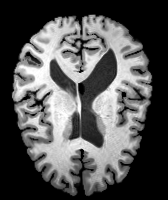

Brain MRI experiment: We also evaluate our method on the MindBooggle101 [4] brain MRIs with 32 cortical regions. We fuse corresponding segmentation labels of the left and right brain hemispheres. MindBoogle101 consists of images from multiple datasets, e.g., OASIS-TRT-20, MMRR-21 and HLN-12. After removing images with incorrect labels, we obtain a total of 85 images. We use 5 images from OASIS-TRT-20 as validation set and 15 as test set. We use the remaining 65 images for training. Manual segmentations in the N=1 and N=21 experiments are only from the MMRR-21 subset; this simulates a common practical use case, where we only have few manual segmentations for one dataset and additional unlabeled images from other datasets, but desire to process a different, new dataset. All images are 1mm isotropic, affinely-aligned, histogram-matched, and cropped to size . We apply sagittal flipping for training data augmentation. We use the same loss weights as for the knee MRI experiment except for , since cross-subject brain registrations require large deformations and hence less regularization.

Results: All trained networks are evaluated using Dice overlap scores between predictions and the manual segmentations for the segmentation network, or between the warped moving segmentations and the target segmentations for the registration network. Tabs. 1 and 2 show results for the knee and brain MRI experiments respectively in Dice scores (%). Fig. 2 shows examples of knee MRI registrations and brain MRI segmentations.

Brain results: Dice scores for segmentation and registration increase by about 2.6 and 3.5 respectively for the cortical structures of the brain MRIs.

One-shot learning: In the one-shot experiments on both datasets, reasonable segmentation performance is achieved; moreover, DA increases the Dice score over unsupervised registration by about 2.7 and 1.8 on the knee and brain data respectively. This demonstrates the effectiveness of our framework for one-shot learning.

Qualitative results: DA achieves more anatomically consistent registrations than the mono-networks on the knee (Fig. 2) and Brain MRI samples (see supplementary material).